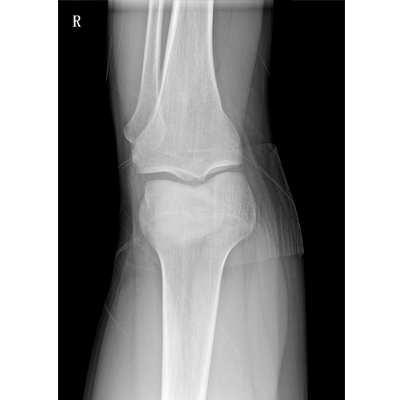

● 數(shù)字化無線平板成像,操作簡便,成像質(zhì)量高